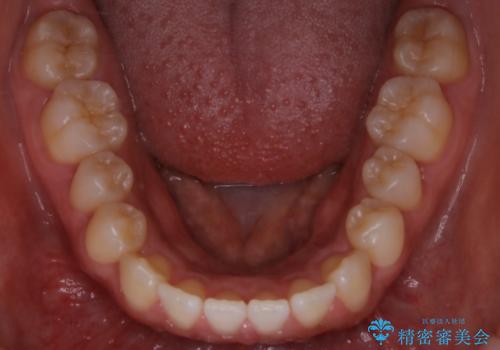

インビザライン矯正 前歯のすきっ歯を治したい

- 上顎の前歯のすきっ歯を治したいとのことで来院されました。

前歯の隙間を閉じる矯正治療の場合、インビザライン適用症例のためインビザラインによる治療をご提案しました。

後戻り防止のため、上唇小帯切除も併用しています。